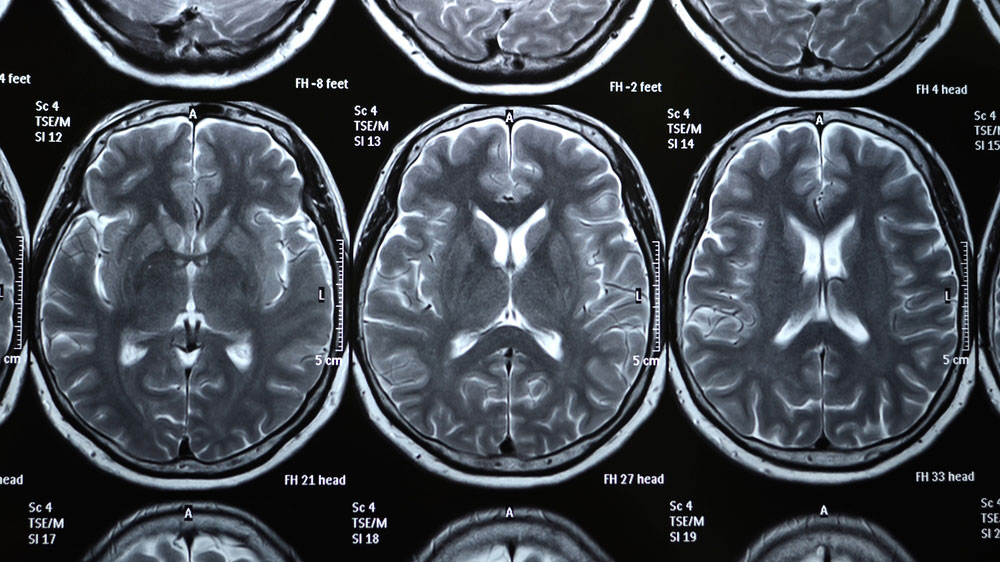

The trials will match patients with a treatment according to findings on imaging, such as hemorrhage, brain bruising or neuro-inflammation, as well as the presence of blood-based biomarkers.

“We are entering a new era of precision medicine in the research and treatment of TBI,” Manley said. “Using novel and developing tools in the fields of imaging, biomarkers and genomics, we are better able to diagnose patients and test treatments to relieve the substantial burden that patients carry for life.”

TRACK-TBI has built a network of 3,000 patients whose diagnoses cover the spectrum of mild-to-severe TBI, and developed a standardized approach to analyze imaging, clinical data, biospecimens and treatment outcomes across research sites. Additionally, its databases include what may be the world’s largest serial collection of brain scans and biospecimens of TBI patients.